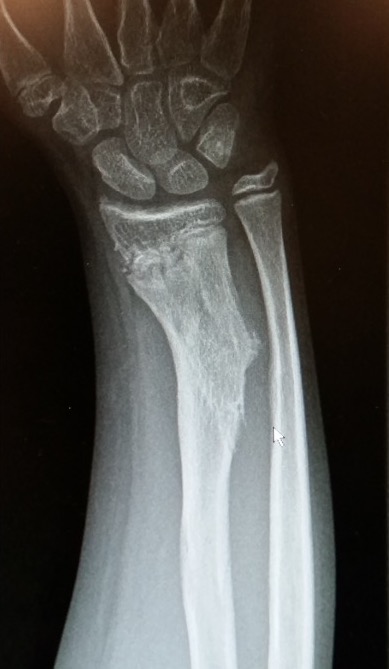

Forearm

- ulnar shortening / radial bowing / ulnar deviation of wrist

- can get radial head dislocation / carpal slip

Osteochondromas Forearm 1Osteochondromas Forearm 2

Incidence

Jo et al J Hand Surg Am

- 53 pediatric patients with HME

- 10% incidence of radial head dislocation